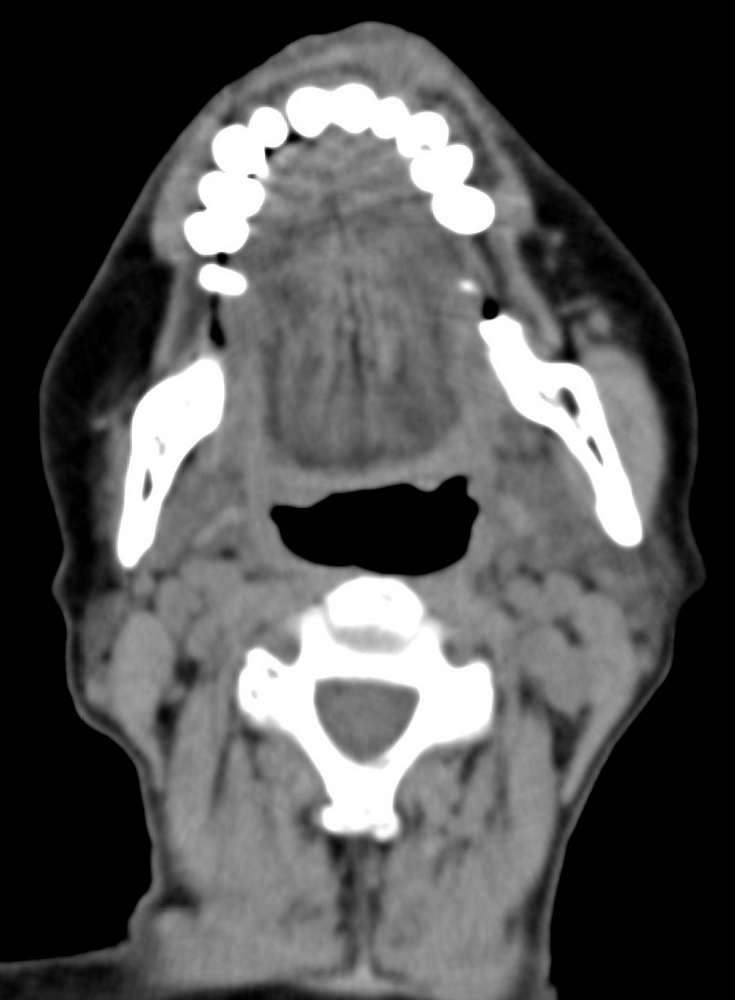

女,68岁。发现上唇无痛性肿块2年多,查体局部皮肤隆起,其余未见异常。

病灶ct值约42hu。

病理结果:唾液腺混合瘤。